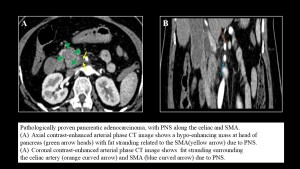

Pancreatic cancer

The tendency of pancreatic cancer to spread along nerves is likely attributable to the dense network of neural plexuses surrounding the pancreas. In pancreatic ductal adenocarcinoma, the most frequent sites of perineural spread are the celiac plexus and the plexus pancreaticus capitalis . Except for the celiac ganglia, the neural plexuses are not directly visualized at imaging, with the mesenteric arteries they follow serving as surrogate landmarks for detection, where PNS manifest as wispy increased attenuation or confluent perivascular soft tissue.